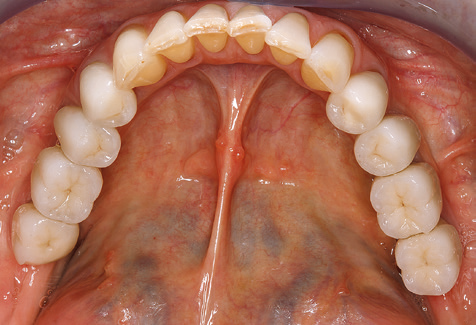

A 52-year-old patient presented in our clinic for the first time in 2004 following tooth loss in the third quadrant, expressing a desire for a new prosthetic restoration. Periodontal and radiological diagnostics revealed the need for extensive periodontological treatment. In addition, teeth 48, 28 and 27 were attributed a very poor prognosis and were subsequently extracted (Fig. 1). Following the successfully completed, systematic periodontological treatment, a fixed dental implant was inserted with the introduction of five implants in tooth regions 35, 36, 37, 46 and 47. Prosthetic treatment of the natural teeth was effected with veneered zirconium dioxide ceramic crowns; the implants were composed of two-piece, individual zirconium dioxide abutments and similarly veneered crowns made of a zirconium dioxide ceramic (Cercon base colored, Dentsply Sirona Lab). Definitive insertion of the prosthetic restoration occurred in 2005.

Due to the presence of periodontal disease, SPT was performed every three months in the first years following the insertion. The patient demonstrated a high degree of motivation and good compliance. The pocket depths recorded annually revealed a stable periodontal situation with a BOP index of below five per cent. On the basis of the stable periodontal situation and good cooperation on the patient’s part, the recall interval was extended to every six months as of the sixth year of the prosthetic function phase. Following the change in the recall interval, the respective annual documentation of the periodontal status continued to reveal a stable periodontal situation with no increase in the pocket depths and a BOP index below five per cent (Fig. 2a and b).

The ten-year check-up revealed no indications of advancing clinical attachment loss or peri-implant bone substance loss (Fig. 3).

Standardised and regular risk-adapted care in the scope of SPT is the key to treatment success for the clinical long-term success in periodontically compromised patients. This is particularly true for patients fitted with implants following successfully completed periodontal treatment (Fig. 11a and b).